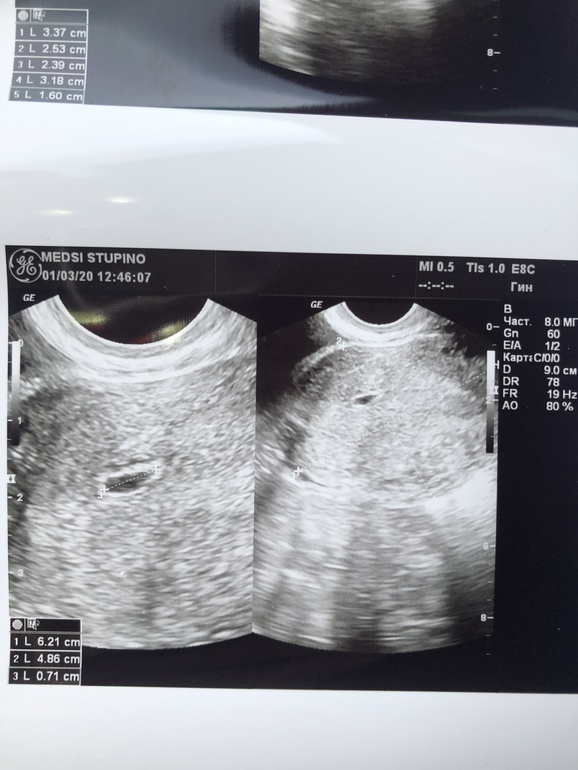

Узи на 5 ак неделе)

Плодное яйцо 7 мм. Маточная беременность) хорион кольцевидный, срок на момент узи, по измерениям врача - 5 нед 1 день.

Эмбрион четко не визуализируется.

Вот наше «щястье» долгожданное ❤️